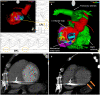

Case presentation: We hereby present the case of a 73-year-old patient implanted with a mitral valve prosthesis, a cardiac resynchronization therapy-defibrillator, and a cardiac contractility modulation device, who was successfully treated with STAR for recurrent drug and CA-resistant MMVT in the setting of advanced heart failure and a giant left atrium V体育安卓版. We report a 2-year follow-up and a detailed dosimetric analysis. .

Conclusion: Our case report supports the early as well as the long-term efficacy of 25 Gy single-session STAR. Despite the concomitant severe heart failure, with an overall heart minus planned target volume mean dosage below 5 Gy, no major detrimental cardiac side effects were detected V体育ios版. To the best of our knowledge, our dosimetric analysis is the most accurate reported so far in the setting of STAR, particularly for what concerns cardiac substructures and coronary arteries. A shared dosimetric planning among centers performing STAR will be crucial in the next future to fully disclose its safety profile. .